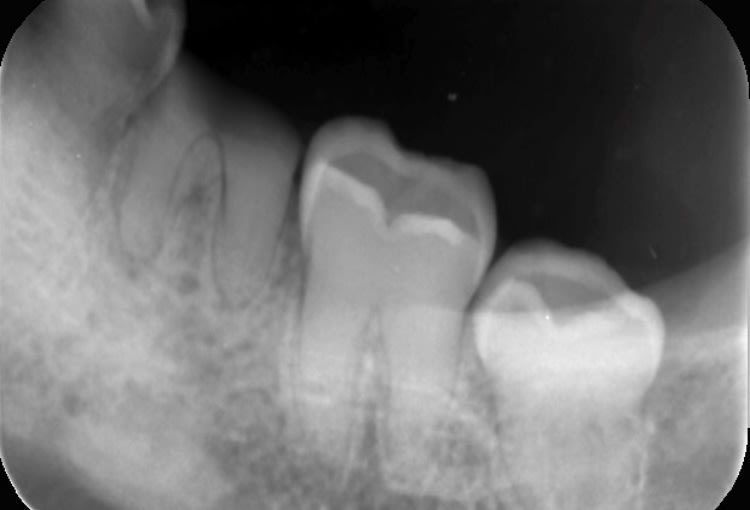

Radio 36